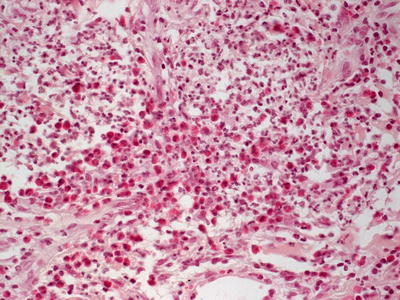

This group of disorders includes iododerma and bromoderma. The histologic features are quite similar, and they will be described together. The epidermis is hyperkeratotic and demonstrates pseudoepitheliomatous hyperplasia in some cases, or it can be entirely normal in others [6]. Within the dermis and occasionally within the epidermis, there is a brisk lymphohistiocytic infiltrate with abundant eosinophils and neutrophils (Figs. 19.1 and 19.2). Intraepidermal abscesses are frequently encountered [2, 4].

Fig. 19.1

A dense dermal infiltrate of neutrophils and eosinophils is present in iododerma

Fig. 19.2

Iododerma demonstrates abundant and diffuse dermal neutrophils and eosinophils